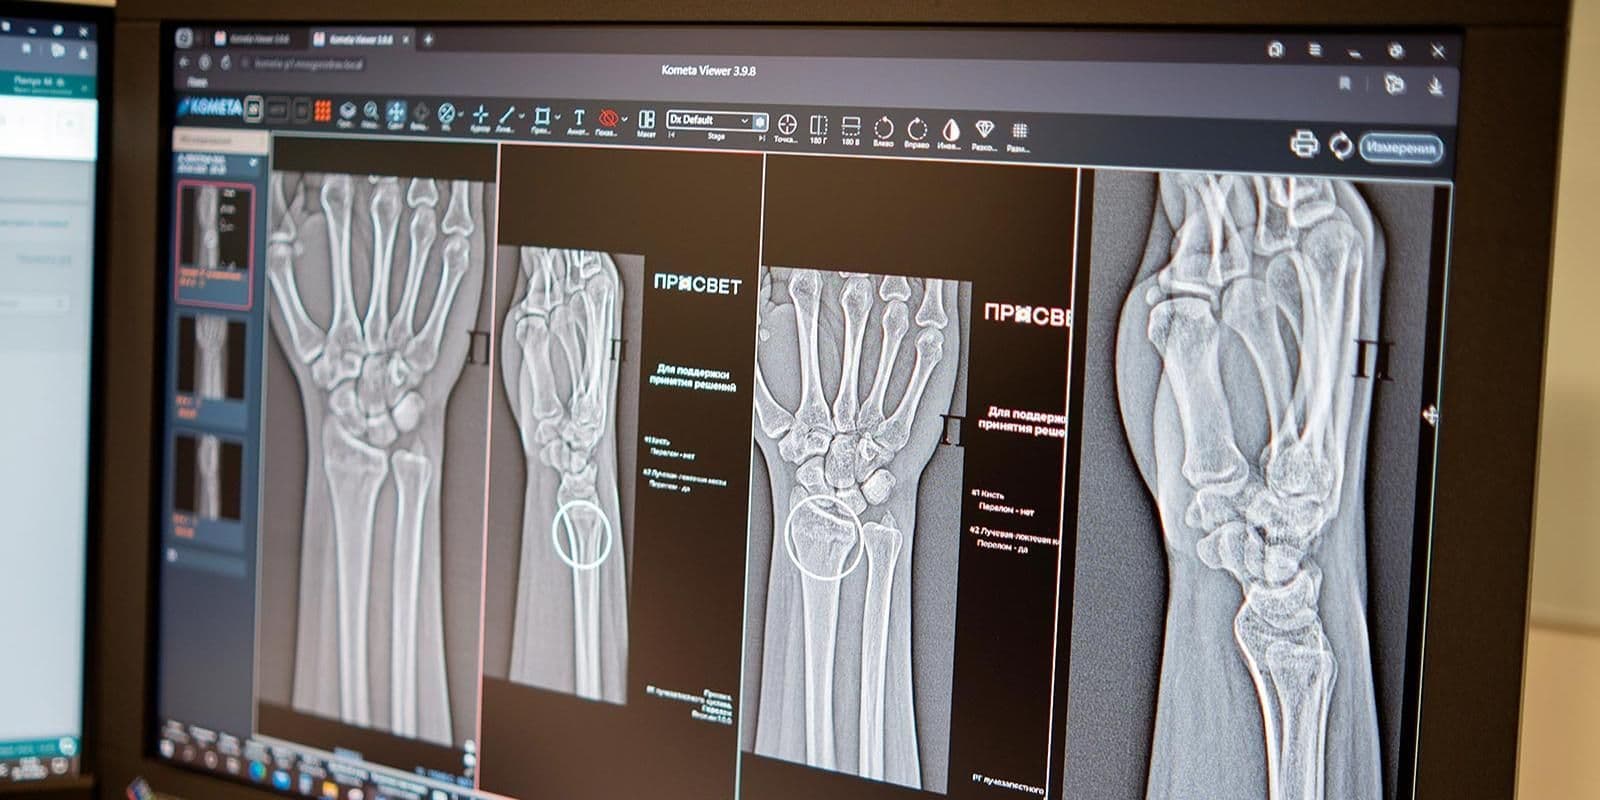

«Алгоритмы автоматически отметят поврежденные участки и выполнят необходимые измерения, даже если на одном снимке присутствуют признаки сразу нескольких переломов. Сегодня в распоряжении московских рентгенологов уже более 60 ИИ-сервисов. Одни отличают «норму» от проявления заболевания, другие, например, могут измерять границы и размеры патологии. Сервисы применяются по 43 клиническим направлениям»Анастасия Раковазаммэра Москвы

Новые ИИ-сервисы:

- анализируют снимки

- помогают выполнить необходимые расчеты и быстрее описать снимки,

- могут заметить даже самые минимальные трещины,

- акцентируют внимание врача на том, что в этой области не один, а несколько переломов.